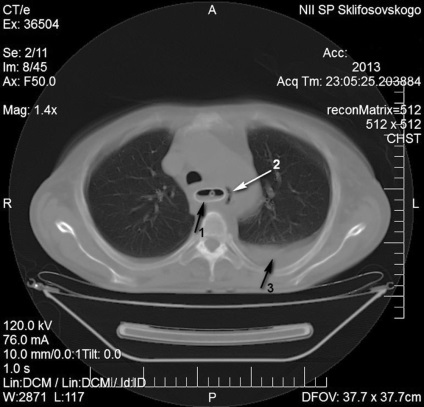

IV stádiumban nyelőcsőrák felvett betegek sürgősségi SRI utáni 7. napon endoszkópos bougienage és SP klinikai-instrumentális mediastinitis állítható képet (ábra. 1).

Kezelés Intézet Sürgősségi ellátás végrehajtása három szakaszból áll. Először is, hogy biztosítsa a megfelelő enterális táplálás készült Laparotomiát Nissen LF, gastrostomia Kader. Miután javítása tápláltsági állapota, köpölyözés aspirációs tüdőgyulladás második szakaszban végzett jobb thoracotomia, reszekció mellkasi nyelőcső, egy bal oldali kolotomiyu, megszüntetése tracheo fistula a műanyag légcső defektus izom- periosteum lebeny, traheofissuru képződik a T-alakú cső. Működés közben a stent távolítani. Miután 8 hónappal a beteg kialakított mesterséges nyelőcső a vastagbél annak retrosternalis helyét.